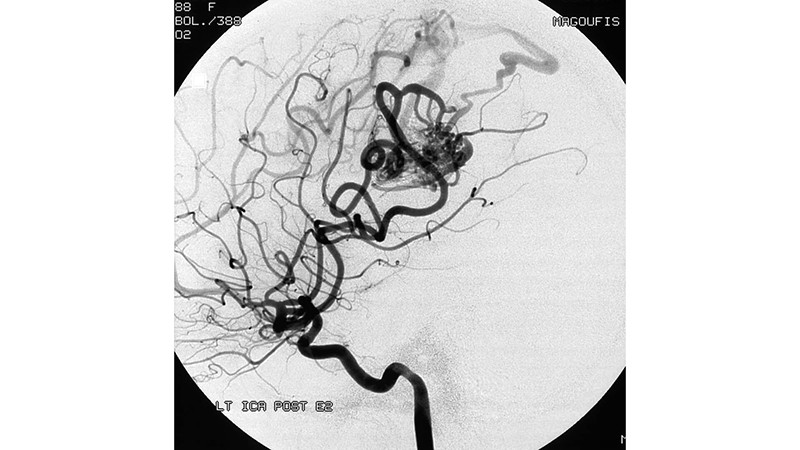

- Εκλεκτικός καθετηριασμός και εμβολισμός με κυανοακρυλική κόλλα του μεγαλύτερου οπισθίου τροφοφόρου κλάδου, με ικανοποιητική διείσδυση στην φωλεά.

- Εικόνα μετά τον εμβολισμό του οπισθίου κλάδου.